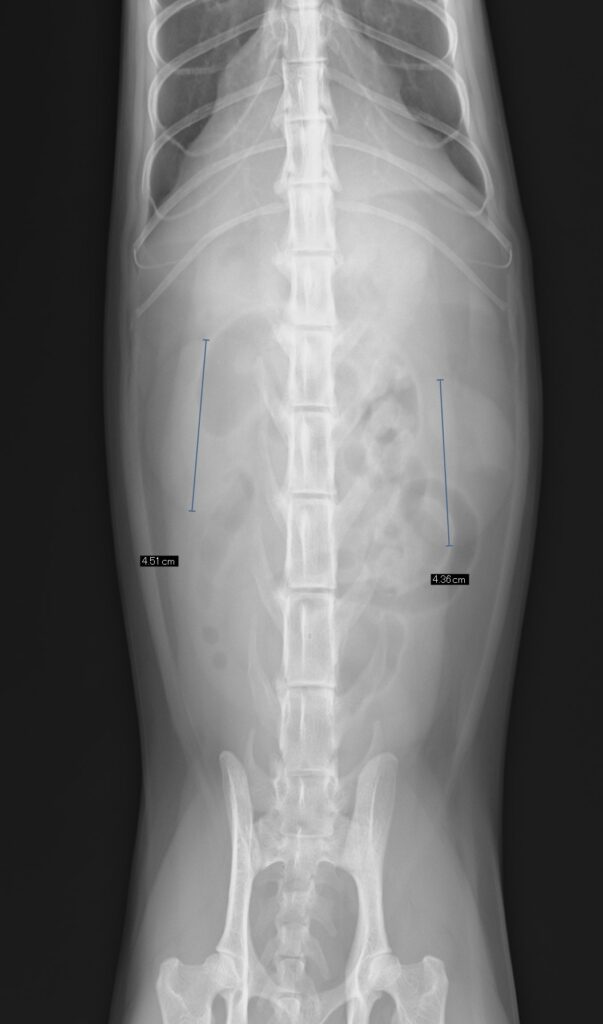

下の画像、左は健康なネコちゃん、右は慢性腎臓病のネコちゃんのレントゲンです。

右側の写真では腎臓の萎縮がみられます。また腎結石(矢印)もみられます。